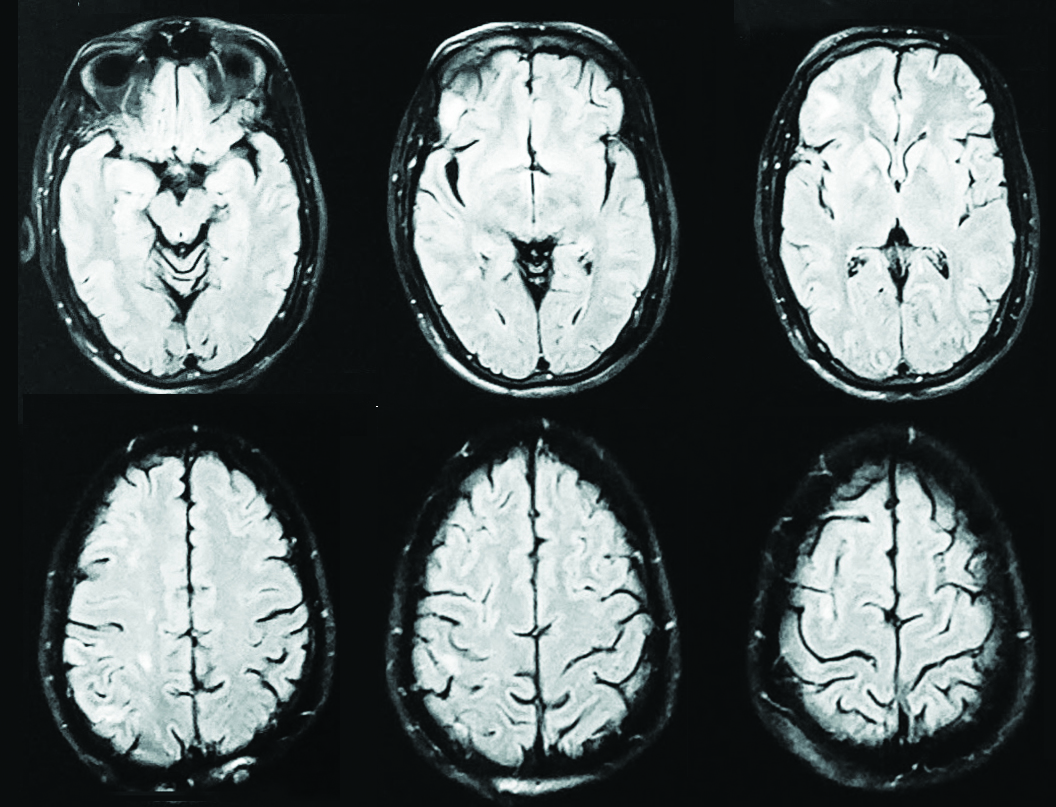

MRI brain revealed multiple acute to subacute lacunar infarcts in right Fronto- Parietal cortical and subcortical region, right Ganglio-Thalamo-capsular region and right periventricular white matter. Absent flow void was noted in right ICA with FLAIR hyper intensive signal noted within its lumen suggestive of an occlusion (Figure 2).

Figure 2: MRI report showing multiple lacunar infarcts in right Fronto-Parietal cortical and subcortical region, right Ganglio- Thalmo capsular region and right periventricular white matter.